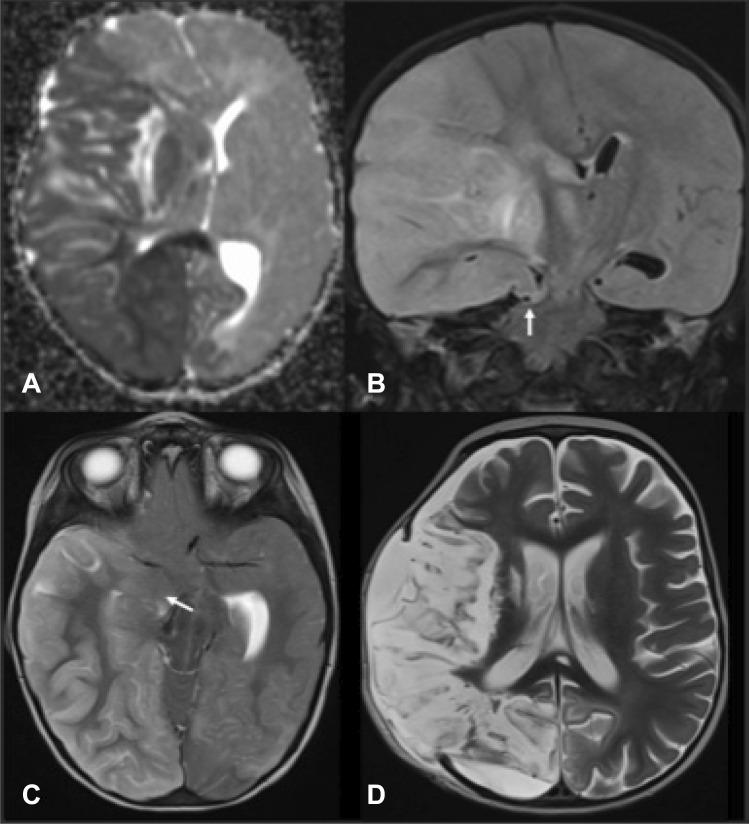

We performed an extensive literature review on pediatric malignant arterial ischemic stroke (pmAIS) and selected 26 articles reporting 97 cases. Gathering the data together, a 67% mortality rate is observed without decompressive therapy, contrasting with a 95.4% survival rate with it. The median modified Rankin score (mRS) is 2.1 after surgery with a mean follow-up of 31.8 months. For the 33% of children who survived without surgery, the mRS is 3 at a mean follow-up of 19 months. As an illustrative case, we report on a 2-year-old girl who presented a cardioembolic right middle cerebral artery stroke with subsequent malignant edema and ongoing cerebral transtentorial herniation in the course of a severe myocarditis requiring ECMO support. A DCH was done 32 h after symptom onset. At the age of 5 years, she exhibits an mRS of 3.